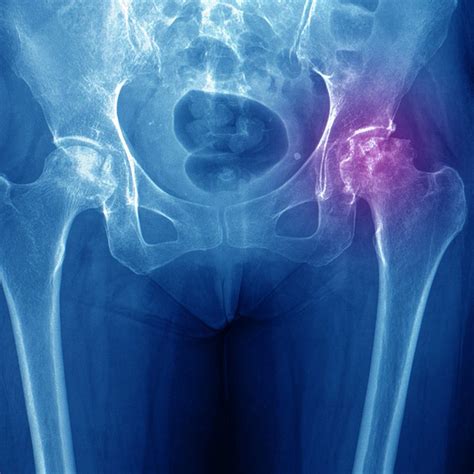

• Avascular Necrosis: Also known as osteonecrosis, this condition occurs when bone tissue dies due to a lack of blood supply. It can be caused by trauma, alcoholism, or certain medications.

• Imaging Studies: X-rays, MRI, and CT scans can help visualize the affected tissue and identify areas of avascularity.